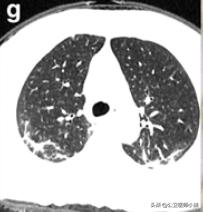

根据感染的不同程度累积一个或多个肺叶

肺部感染涉及多个肺叶-1